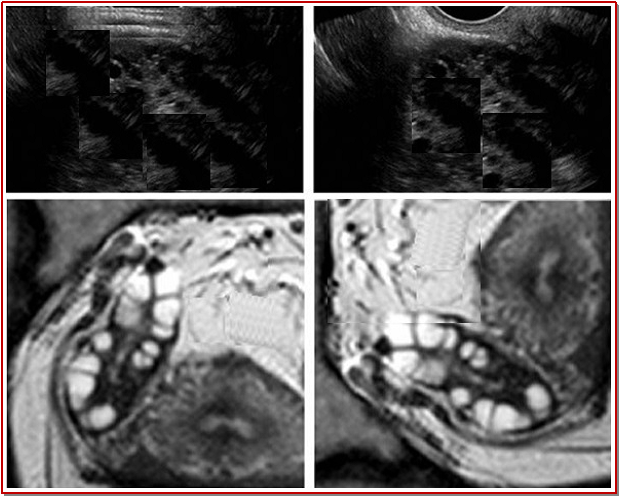

In the present study 32 women with polycystic ovary syndrome were treated with glabridin (10 µM) daily for 12 months. The results revealed a significant reduction in serum testosterone from 95.3 ± 23.6 to 49.8 ± 12.7 ng/dL and fasting insulin concentrations from 12.3 ± 5.2 to 8.11 ± 3.42 U/mL after glabridin treatment. It also leads to a marked improvement in insulin resistance indices and reduction in hirsutism score from 12.8 ± 3.2 to 7.0 ± 3.5. More interestingly, all the women reverted to regular menstrual cycles. The sex hormone-binding globulin level increased significantly from 23.1 ± 5.6 to 52.5 ± 15.8 nmol/L after glabridin treatment. The levels of serum hsCRP decreased from 0.32 ± 0.08 to 0.06 ± 0.01 mg/dL and that of endothelium-dependent vascular responses from 17.2 ± 4.3 to 8.8 ± 2.4% after glabridin treatment. Therefore, glabridin acts as a potent candidate for the improve-ment of insulin sensitivity and androgen production.